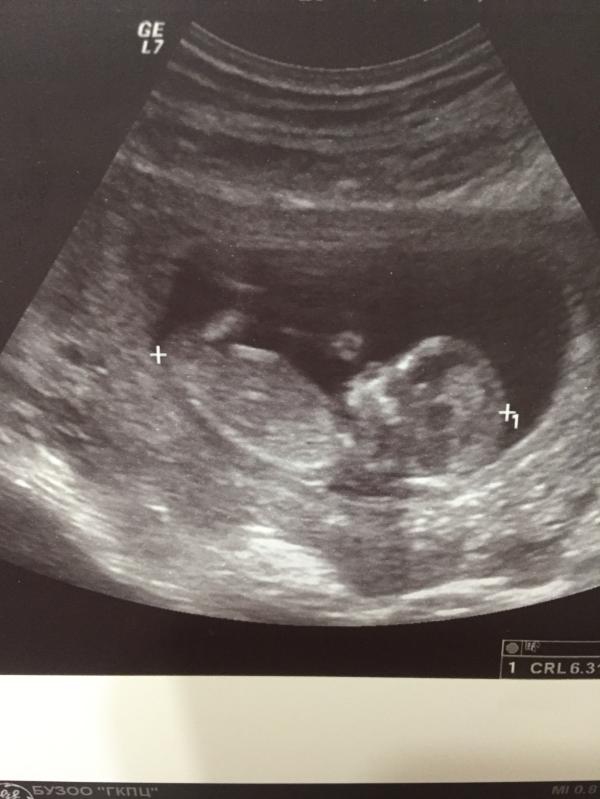

Моя креветочка😍

Первый скрининг прошел хорошо🙏 Надеялась, что смогут разглядеть пол, но нет😟 В прошлый раз я на 100% была уверена, что там девочка. А в этот раз не знаю 🤷♀️ Мне уже 2 раза мальчик снился. Так что любопытство меня съедает. Может быть не сдержусь и через пару недель пойду платно узи сделаю🙈